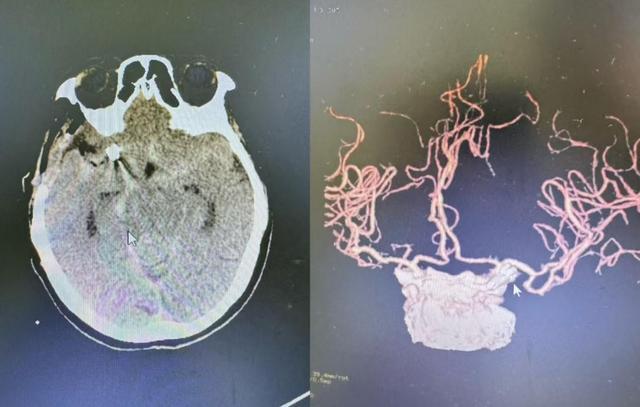

入院后,紧急安排患者行头部CT检查,检查结果提示蛛网膜下腔出血。神经外科刘银川副主任医生第一时间赶赴现场会诊后,高度怀疑为动脉瘤破裂出血,为进一步明确诊断,医院立即为患者安排颅脑 CT 血管成像(CTA)检查,最终精准确诊为右侧颈内动脉交通段动脉瘤。

(术后复查影像)